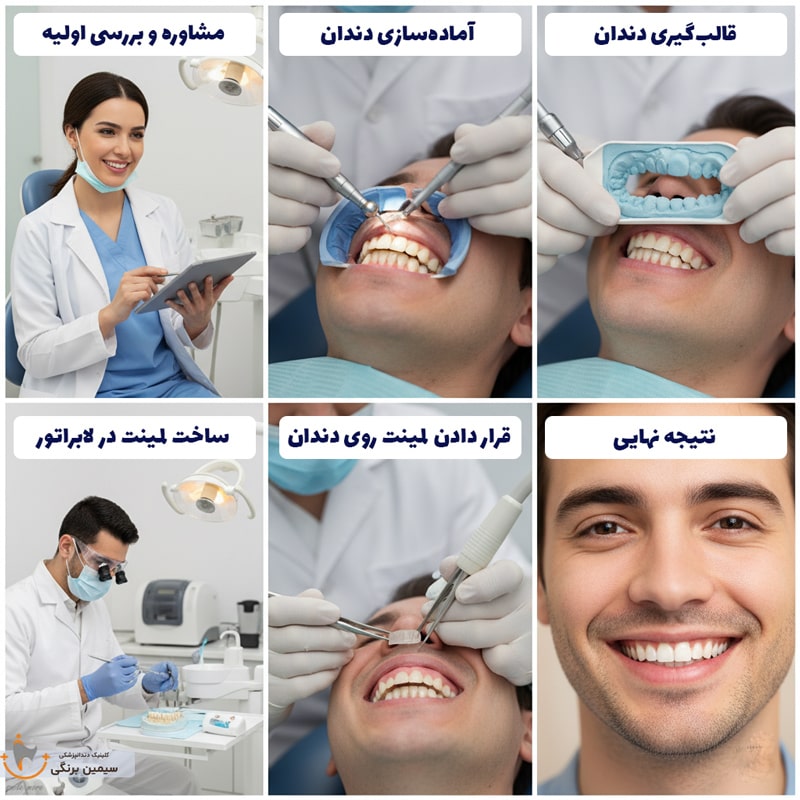

مراحل انجام لمینت دندان

۱. معاینه اولیه:

اولین مرحله در فرایند لمینت ، معاینه اولیه بیمار توسط دندانپزشک است. در این مرحله، دندانپزشک با بیمار گفتوگویی دقیق و کامل انجام میدهد تا اطلاعاتی دربارهی انتظارات بیمار از درمان، وضعیت فعلی دهان و دندان، خواسته ها و نیازهای او، دامنهی درمان، برآورد تقریبی هزینهها و روند کلی درمان بهدست آورد.

رفع ابهامات و پاسخ به سؤالات ذهنی بیمار در این مرحله، باعث میشود که درمان با احساس راحتی و بدون نگرانی آغاز شود. همچنین پیش از شروع لمینت، اگر نیاز به انجام سایر درمانهای دندانپزشکی مانند جرمگیری، پر کردن دندان یا درمان های پایه ای دیگر وجود داشته باشد، ابتدا این مراحل تکمیل میشوند.

۲. برنامه ریزی و طراحی:

۳. قالب گیری و ساخت لمینت دندان:

پیش از ساخت لمینتهای دندانی، اندازهگیری دقیق دهان و دندانهای بیمار انجام میشود. برای این منظور، معمولاً از دو روش استفاده میشود:

- روش کلاسیک: که در آن از مواد قالبگیری نرم استفاده میشود و این ماده درون دهان بیمار قرار میگیرد تا شکل دندانها را ثبت کند.

- تکنولوژی CAD-CAM: در این روش، فضای داخل دهان با دوربینهای بسیار کوچک و دقیق اسکن میشود و اطلاعات آن به صورت دیجیتال به نرمافزار کامپیوتری منتقل میگردد.

با استفاده از این تکنولوژی پیشرفته، تمام مراحل از قالبگیری تا ساخت لمینت در لابراتوار با دقت بالا و پشتیبانی نرمافزارهای مخصوص انجام میگیرد.

اندازهگیریهای انجامشده به لابراتوار فرستاده میشود و تکنسین دندانساز لمینتها را در رنگ و مدل دلخواه، با دقت بالا تولید میکند. این فرایند بسته به شرایط و تعداد دندانها معمولاً ۱ تا ۲ هفته زمان میبرد.

۴. نصب لمینت های موقت:

پس از انجام مراحل آمادهسازی و قالبگیری، لمینت های موقت برای بیمار نصب میشوند. دلیل این کار، افزایش حساسیت دندان های طبیعی نسبت به گرما و سرما پس از تراش سطح مینای دندان و همچنین ظاهر غیرطبیعی دندان ها در این مرحله است.

۵. آماده سازی:

پس از تهیه قالب دندانها و ارسال آن به لابراتوار برای ساخت لمینتهای دندانی، مرحله آماده سازی دندان های طبیعی آغاز میشود. پیش از شروع کار، برای جلوگیری از احساس درد، بی حسی موضعی برای بیمار اعمال میگردد. سپس، لایهی مینای دندان به اندازه ضخامت لمینتی که قرار است چسبانده شود، تراش داده می شود.

۶. تست نهایی و اتصال دائم:

در این مرحله، ابتدا لمینتهای موقت از روی دندانها برداشته میشوند. سپس، لمینتهای اصلی که در لابراتوار ساخته شدهاند، قبل از اتصال نهایی روی دندانها امتحان میشوند. در این تست، دندانپزشک سازگاری، فرم و رنگ لمینتها را بهدقت بررسی میکند. در صورت نیاز، اصلاحاتی برای رسیدن به نتیجهی ایدهآل انجام میشود. همچنین در این مرحله، نظر و تأیید نهایی بیمار نیز گرفته میشود.

پس از تأیید نهایی، لمینتها بهصورت دائمی روی دندانهای طبیعی چسبانده میشوند. برای این کار، ابتدا سطح دندان طبیعی بهخوبی تمیز میشود. سپس، ژل اسیدی مخصوص برای مدت ۱۵ تا ۲۰ ثانیه روی دندان قرار میگیرد تا سطح دندان کمی زبر و آماده اتصال شود. پس از آن، ژل اسیدی از سطح دندان پاک شده و دندان کاملاً خشک میگردد.

در ادامه، ژل چسبنده مخصوص با رنگی متناسب با لمینت انتخابشده، روی سطح دندان طبیعی اعمال میشود و لمینت روی آن قرار میگیرد. در نهایت، با استفاده از نور آبی مخصوص (لایت کیور) چسب فعال میشود و فرآیند اتصال نهایی به سرعت و با استحکام بالا تکمیل می شود.